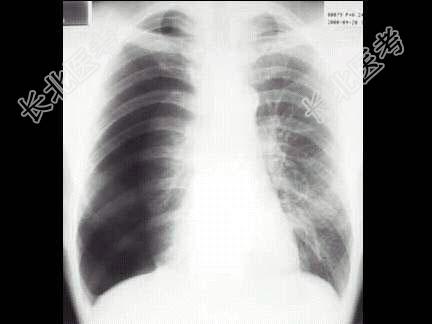

- 单项选择题患者突发胸痛气急,呼吸困难, 胸片如图,最可能的诊断为 ( )

A、右侧肺大泡

B、右侧气胸

C、右侧中央型肺癌并阻塞性肺气肿

D、肺气肿

E、右肺肺炎